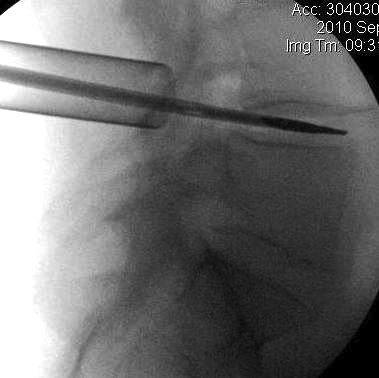

Levels

Careful correlation of clinical and MRI

- level of disc

- side of disc

Iliac Crests L4/5

- mark

- prep with antimicrobial solution

- insert 18G needle into L4/5 interspinous space

- obtain cross table xray to confirm level

- this centres incision